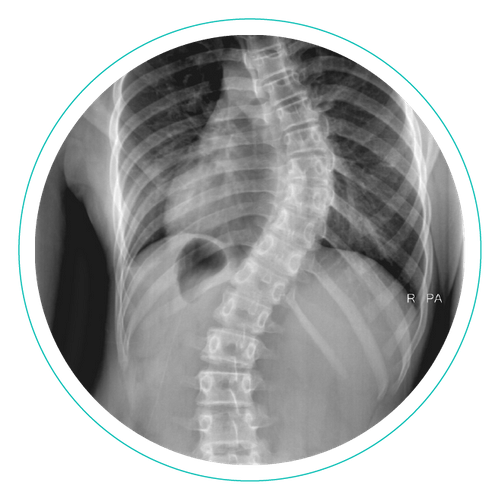

Radiology of Scoliosis ProCredits

From procreditsce.com

Radiology of Scoliosis ProCredits Scoliosis Uspstf In the current issue of jama is the latest recommendation statement by the us preventive services task force (uspstf), 1 and. To systematically review evidence on benefits and harms of ais screening for the us preventive services task force. Treatment of idiopathic scoliosis (cobb angle <50° at diagnosis) in adolescents with exercise (2 small studies) or surgery (no studies) or. Scoliosis Uspstf.